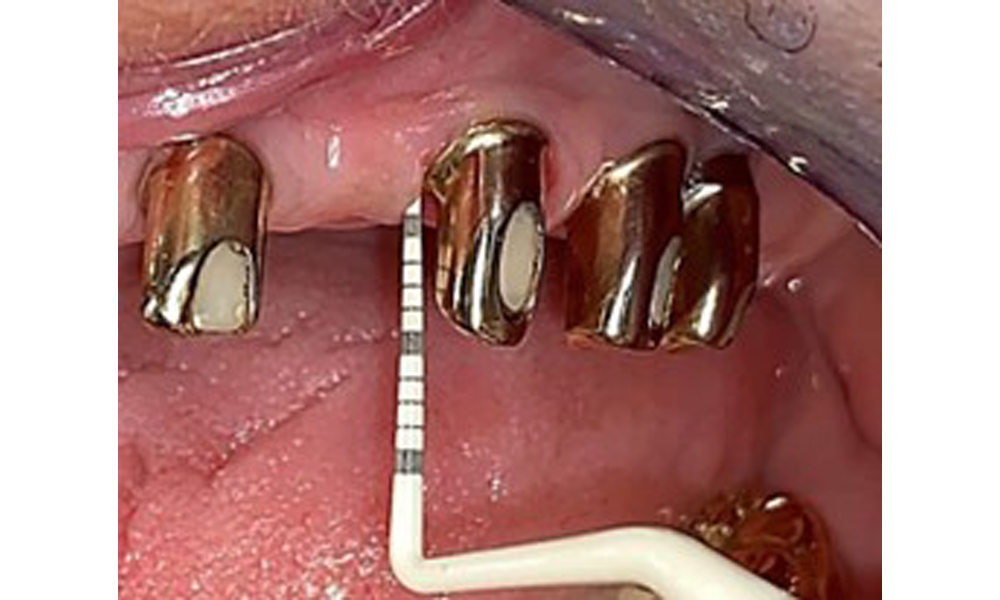

The dental findings are as follows: Combined removable implant and tooth-supported telescopic prostheses on implants 15, 13, 21, 23, 24, 25 and tooth 11 (Fig. 1, Fig. 2, Fig. 3). The patient was fitted with a fixed mandibular denture. Adequate bridges were present over 37 to 34 and 45 to 47 (Fig. 4), the crown margins were intact and there were no active caries. A composite filling with a marginal gap was present on tooth 43. There was mandibular gingival recession, exposing 1 to 3 mm of root surface. This also applies to 11.

Occlusal view: Maxilla with tooth and implant-supported telescopic prostheses.

Fig. 2: Occlusal view: Maxilla with tooth and implant-supported telescopic prostheses